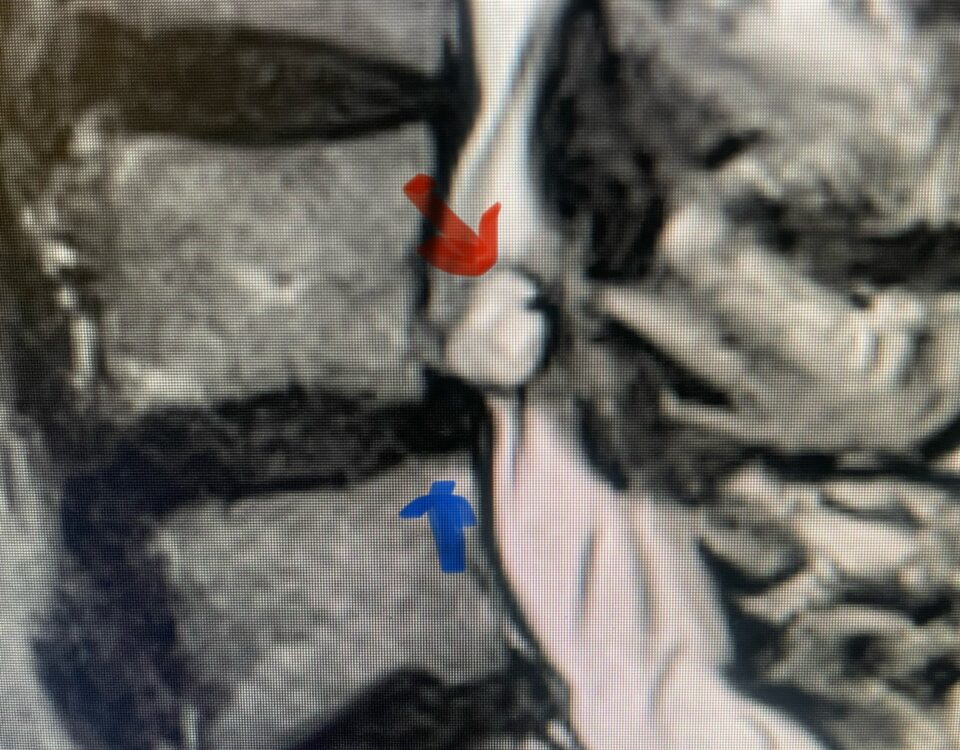

The spinal synovial cyst is one of the most interesting expressions of spinal instability. They emanate from the synovial lining of a degenerated facet joint that […]

People are obsessed with cysts! When you think about it, the body likes to form cysts. Why does this happen? Cysts can form just about anywhere […]